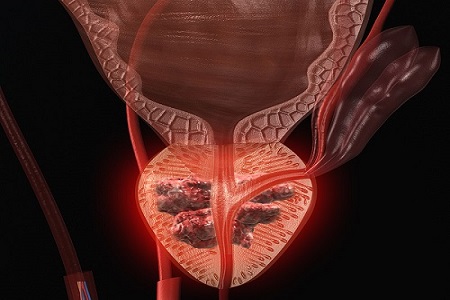

10 عامل خطرآفرین برای سرطان پروستات

تاریخچه خانوادگی می تواند نقش پررنگی در افزایش خطر ابتلا به سرطان پروستات ایفا کند. اگر در خانواده شما سابقه ابتلا به سرطان پروستات وجود دارد، شما نیز در معرض خطر بیشتری برای ابتلا به این بیماری قرار دارید.

اقداماتی برای کاهش خطر سرطان پروستات

مطالعات نشان داده اند مردانی که غذاهایی سرشار از چربی حیوانی، مانند لبنیات و گوشت قرمز، مصرف می کنند، احتمال بیشتری دارد به سرطان پروستات مبتلا شوند.